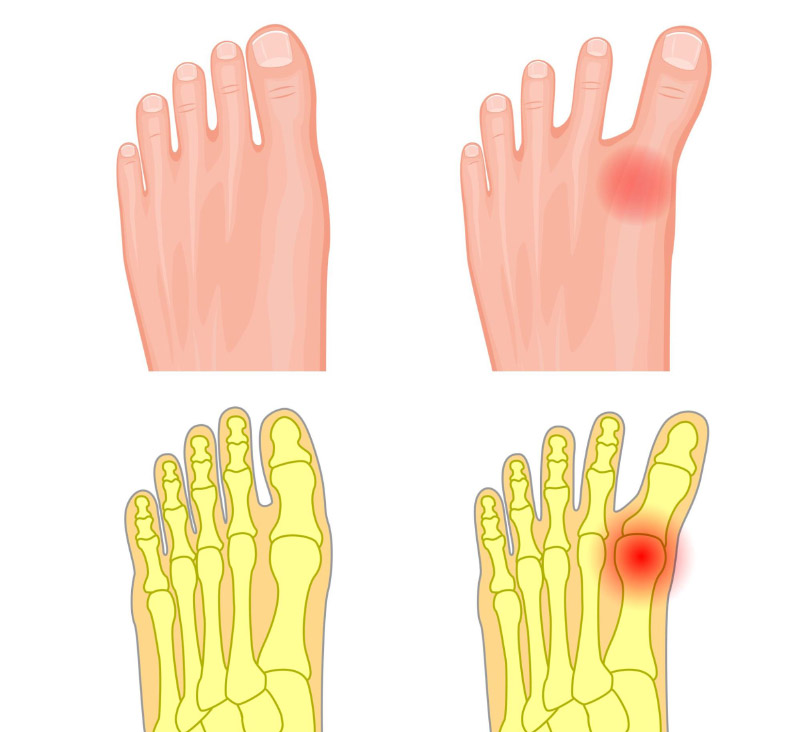

Viêm khớp ngón chân cái (Hallux Rigidus) là tình trạng viêm ở vị trí các khớp ngón chân cái, trong đó phổ biến nhất là khớp nối ngón chân cái với phần còn lại của bàn chân (metatarsophalangeal – MTP), gây đau nhức, khó chịu và cứng khớp. Viêm khớp ngón chân cái là bệnh lý ở ngón chân cái phổ biến thứ hai, chỉ sau vẹo ngón chân cái.

Thông thường, tại các khớp bị viêm, cơ thể sẽ có phản ứng sửa chữa bằng cách phát triển thêm các xương, dẫn đến sự hình thành các gai xương. Khi các gai xương phát triển quá mức, người bệnh có thể gặp khó khăn trong việc uốn cong ngón chân, thậm chí có thể gây hợp nhất khớp dẫn đến giảm sự linh hoạt, tê cứng khớp.

Ngón chân nóng rát, chuyển sang màu hồng đỏ, sưng phù và đau khi chạm vào. Các vết sưng, chai xuất hiện ở ngón chân có thể chèn ép vào các ngón chân khác, khiến cho khớp ở gốc ngón chân cái phình to hơn.

Người bị viêm khớp ngón chân cái có thể gặp khó khăn trong việc uốn cong và cử động ngón chân, thậm chí khiến ngón chân bị biến dạng, cong vẹo do sự tổn thương của xương khớp và sụn. Điều này sẽ ảnh hưởng đến hoạt động đi lại, sinh hoạt của người bệnh.

Thoái hóa khớp (Osteoarthritis – OA) là tình trạng sụn khớp bị bào mòn, theo thời gian sẽ khiến các xương cọ xát vào nhau gây đau và dẫn đến viêm khớp ngón chân. Dưới tác động của thoái khớp và sự hình thành các gai xương, người bệnh sẽ gặp các triệu chứng đau ngón cái khi đi lại, cử động khó khăn, thậm chí gây cứng khớp. (3)